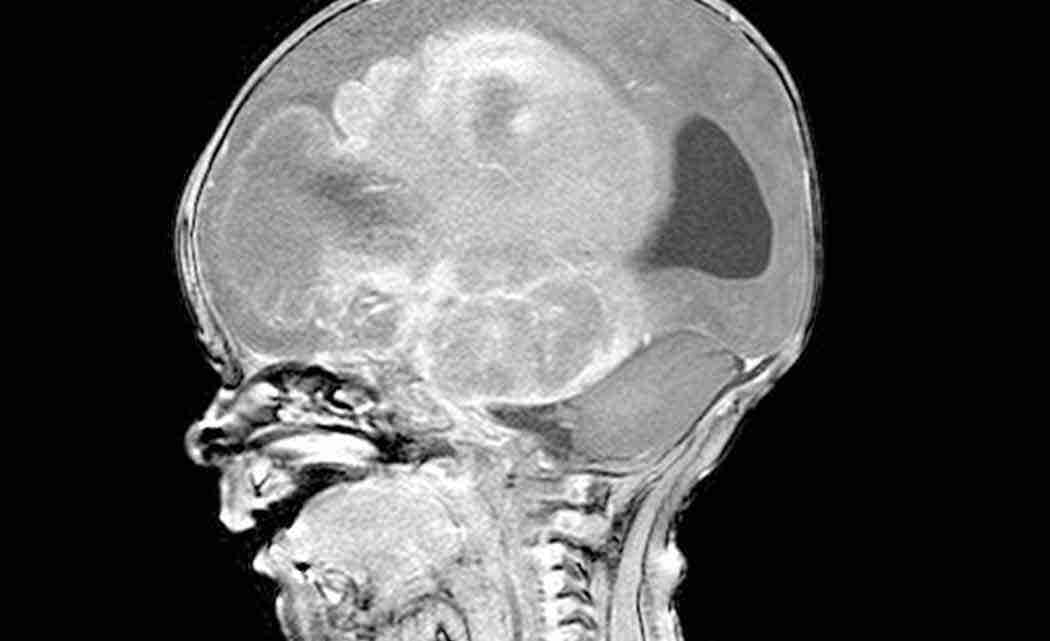

ANN ARBOR, Mich. (AP) _ The family of 4-year-old with an inoperable brain tumor has announced a new foundation to raise public awareness.

Tammi Carr says the foundation’s goal is to build a grassroots network to spread news about intrinsic pontine glioma, and to raise money for families dealing with the rare disease.